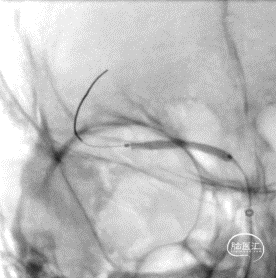

沿微导丝输送赛诺神畅 NOVA颅内药物球扩支架2.25*20mm支架到位,支架输送顺利,全过程无明显张力变化。

6atm缓慢扩张释放支架。

释放支架后造影见支架中段稍有残留狭窄,以8atm缓慢再扩张,残留狭窄消失。